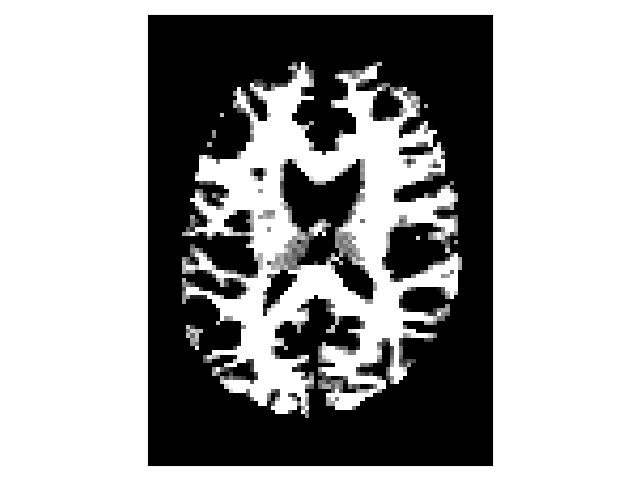

Binary Stopping Criterion#

A binary mask can be used to define where the tracking stops. The binary stopping criterion stops the tracking whenever the tracking position is outside the mask. Here, we show how to obtain the binary stopping criterion from the white matter mask defined above. The binary stopping criterion uses a nearest-neighborhood interpolation at the tracking position.

binary_criterion = BinaryStoppingCriterion(white_matter == 1)

fig.savefig("white_matter_mask.png")

tracking stopping criterion

White matter binary mask.